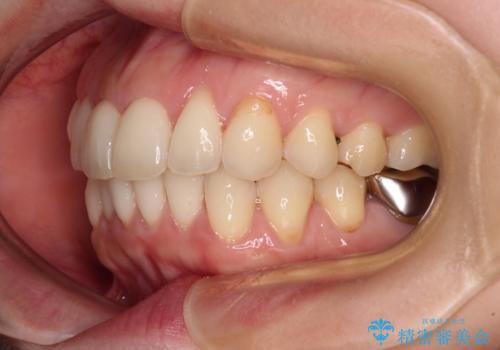

出産をしながら歯列を整える インビザラインによる矯正治療

- 上下の前歯のデコボコを気にして来院された患者様です。

妊娠中であり、途中通院が難しくなる可能性があることから、インビザラインによる矯正治療を行うこととしました。

上下顎歯列全体の後方移動とIPR(歯と歯の間を削る)によってデコボコが解消するように設計しました。